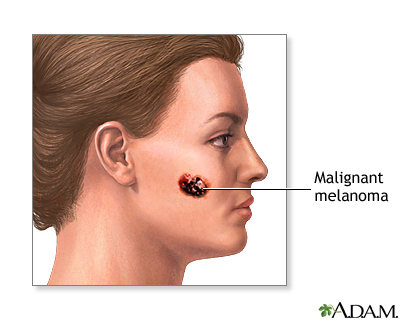

- Lentigo maligna melanoma usually occurs in older people. It is most common in sun-damaged skin on the face, neck, and arms. The abnormal skin areas are usually large, flat, and tan with areas of brown.

A mole, sore, lump, or growth on the skin can be a sign of melanoma or other skin cancer. A sore or growth that bleeds, or changes in color can also be a sign of skin cancer.

- Borders: The edges of the growth are irregular.

- Color: Color changes from one area to another, with shades of tan, brown, or black, and sometimes white, red, or blue. A mixture of colors may appear within one sore.